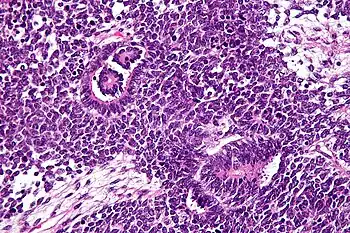

![]() Células tumorales (las células estrelladas) de un nefroblastoma. Microscopía electrónica. | ||

El tumor de Wilms es un tumor maligno que contiene blastema metanéfrico, epitelio y estroma. Es característica su presencia en los glomérulos y túbulos renales rodeado por un estroma celular. El estroma puede incluir músculo estriado, cartílago, hueso, tejido graso y tejido fibroso. El tumor suele comprimir el parénquima renal normal.